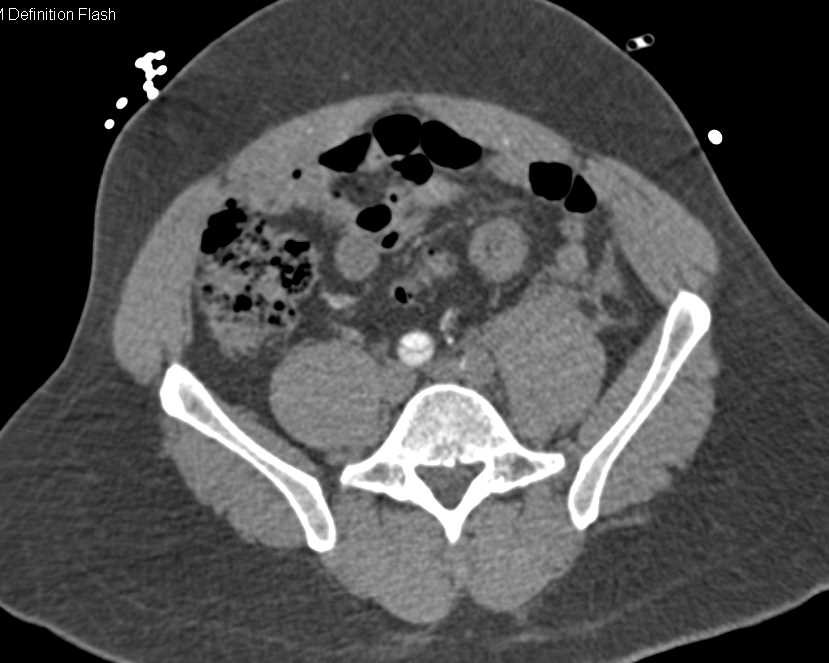

Dissection Lower Abdominal Aorta Extending Into Left Common Iliac Artery